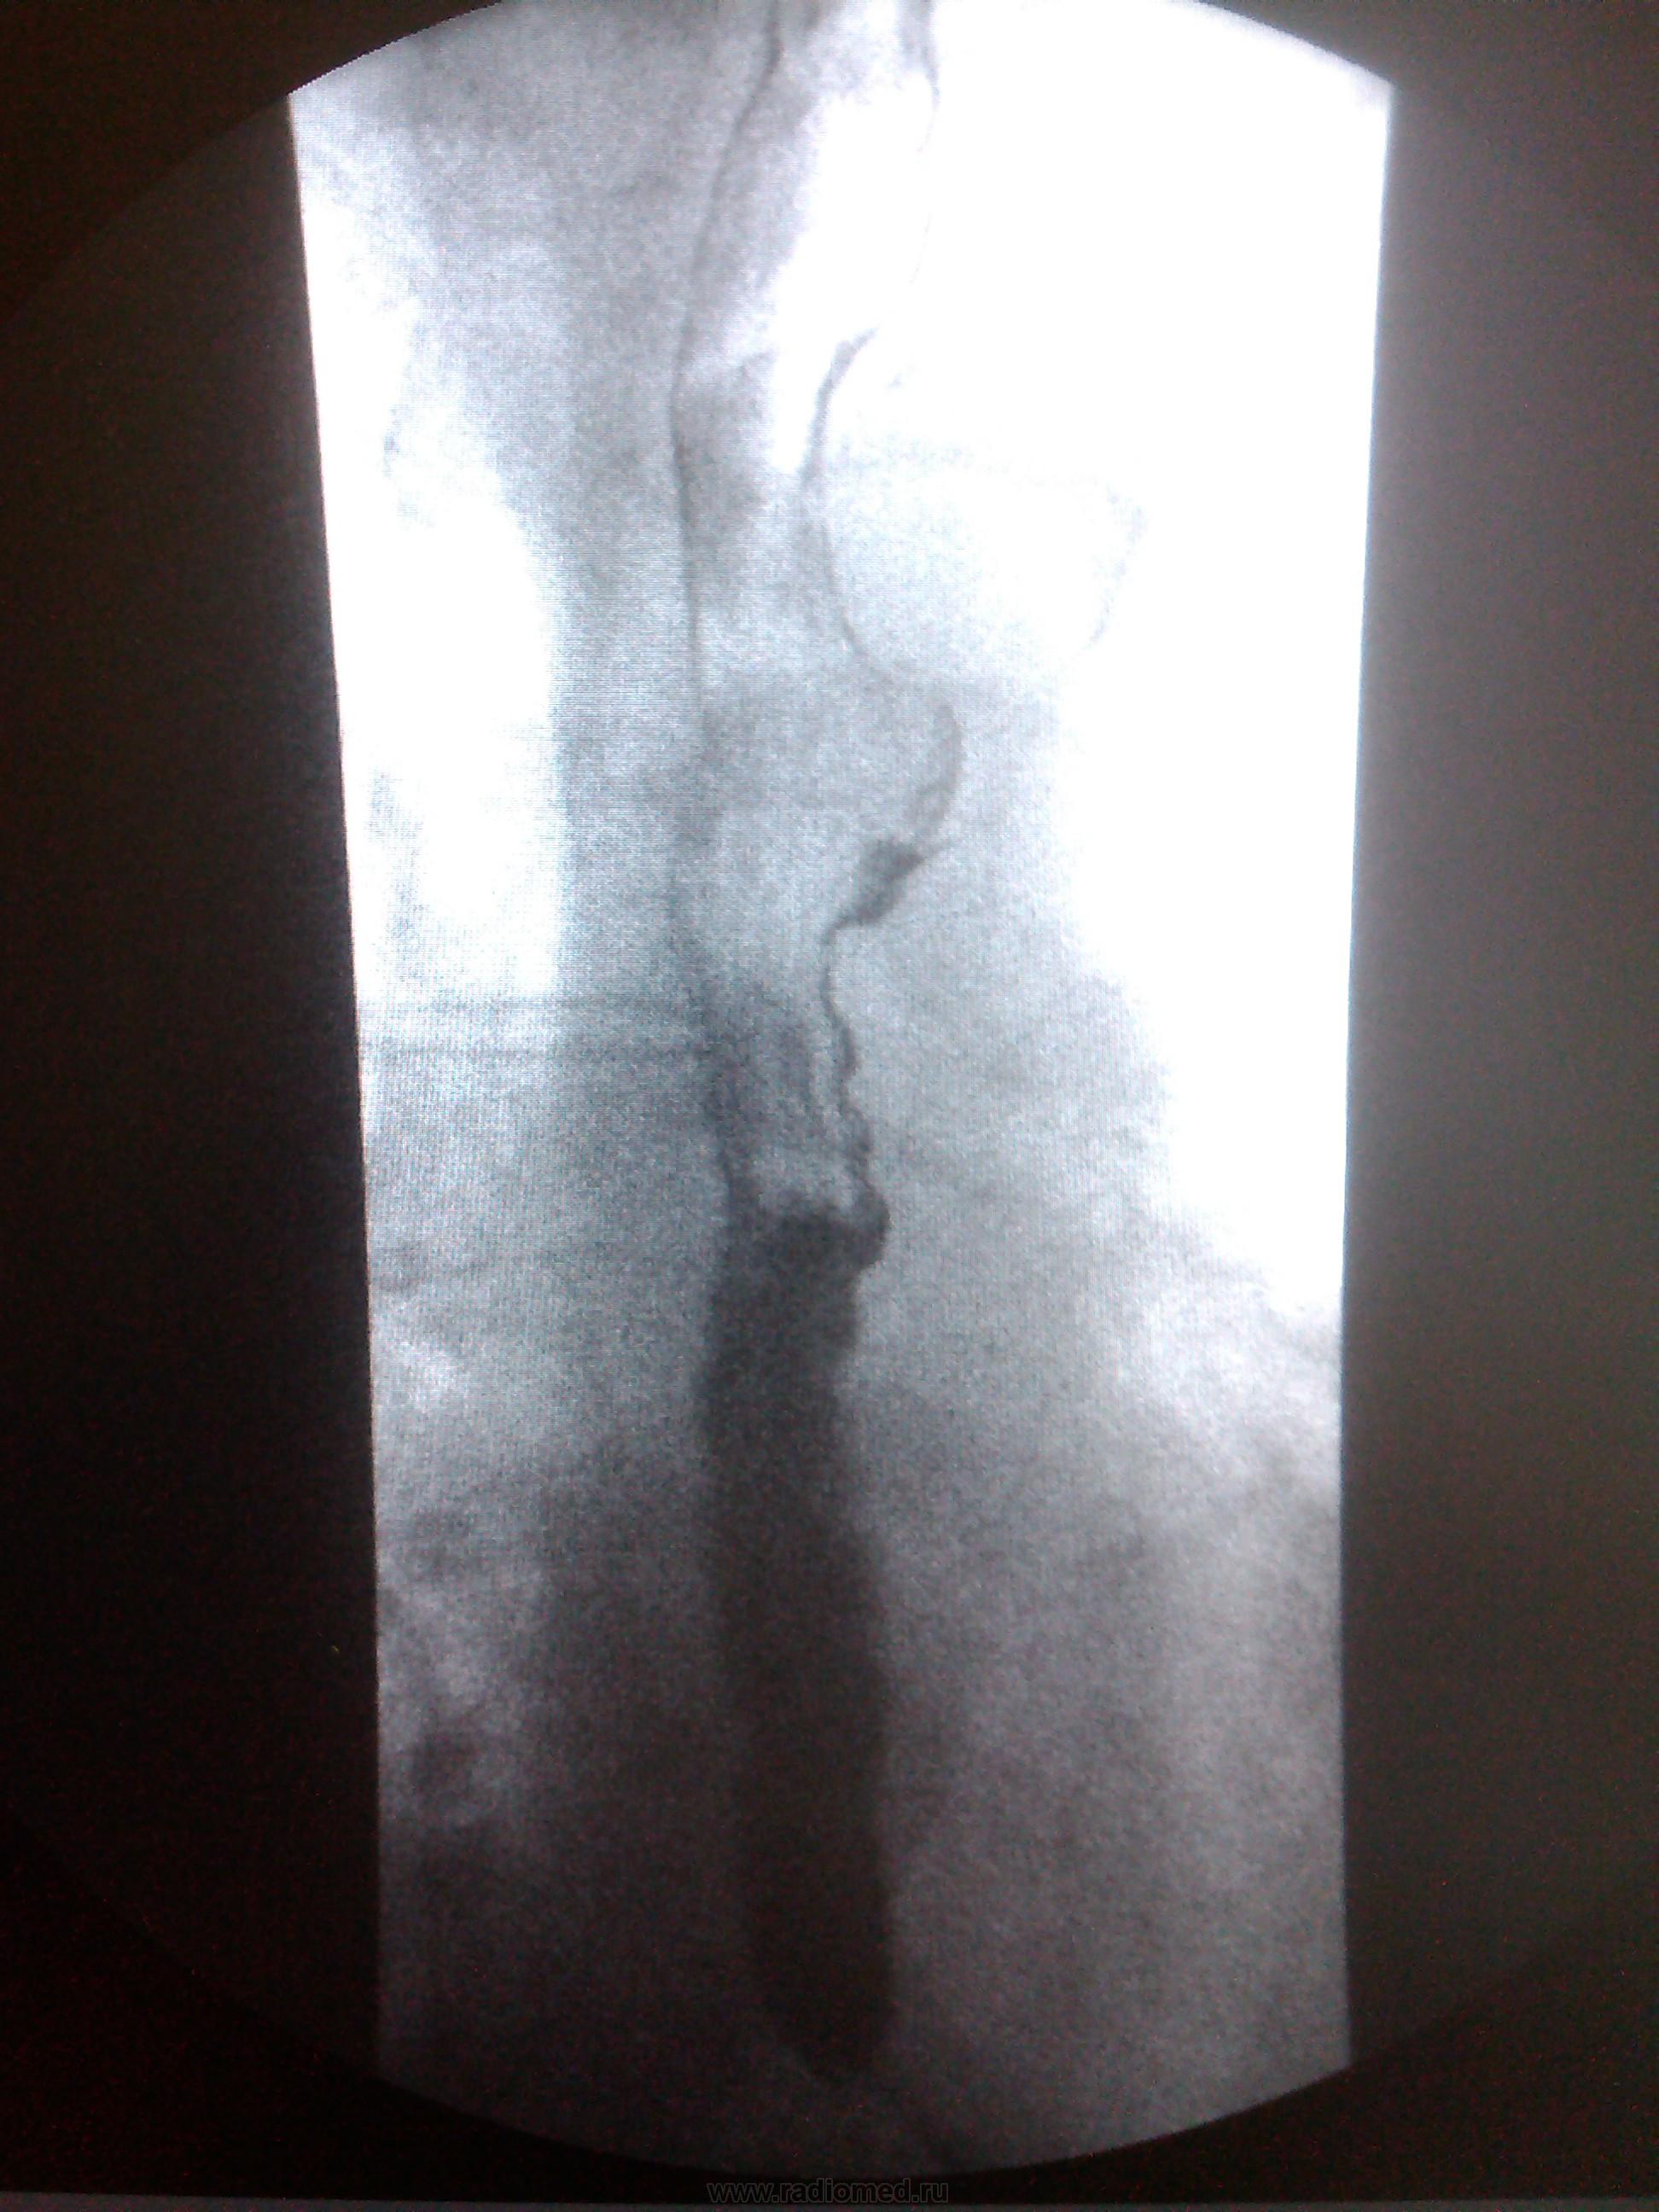

Пациентка, 74 года. Операция по поводу дивертикула пищевода лет 25 назад. Нужны мнения!

Ахалазия кардии, скользящая грыжа пищеводного отверстия диафрагмы, мелкий дивертикул с/3 пищевода - это мнение.

Тракционный дивертикул пищевода. ГПОД. Эзофагоспазм. За ахалазию сомнительно. А вот почему пищевод такой широкий - стоит задуматься.

Может быть он гипотоничный + третичные сокращения вот и выглядит широким, возможно там и эзофагит.

Я такие широкие пищеводы вижу регулярно при склеродермии, например. И клиницисты как бы должны знать о ее существовании, например же. Наше дело - констатировать факты, а их интерпритацию стоит все же оставить другим докторам.

"Нужны мнения!" Мнение: плохо оперировали тогда или: не причину, а следствие. Дивертикул есть и лит есть. ИМХО. А где причина - коллеги по поводу дистального отдела отд. пищевода  уже писали. Теоретически - проблема с 12п. кишкой( по Витебскому)